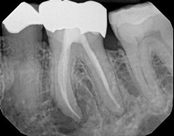

Apicoectomy:

Before, the failed root canal

Immediately after the microsuregery

3-months after shows complete healingThe patient was told by a specialist that the root canal failed, the only option was extraction and an implant. She did not want to do that; she wanted to keep her tooth, after all, it is her front tooth. She found us. We performed an apical microsurgery with the laser. The tooth was saved and is still functioning. This is a poor area for an implant, so much better to save the tooth.